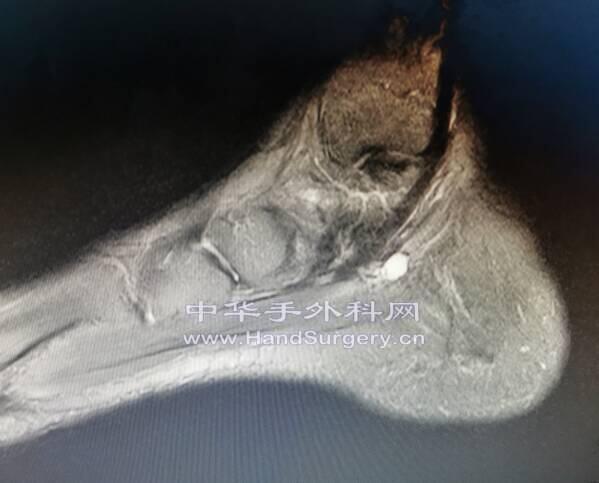

术中见囊肿和足底内侧神经紧密伴行

神经被压迫变扁

磁共振常规扫描显示足底内外侧神经有难度,除非发现病灶薄层高分辨才行,超声相对更有优势一些。